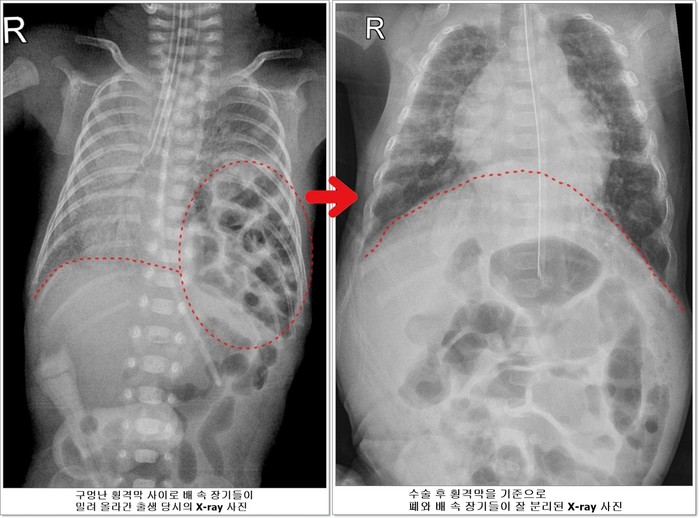

선천성 횡격막 탈장증이란 가슴 안의 심장과 폐를 배 속의 소화기 장기들로부터 분리해주는 횡격막에 선천적으로 구멍이 나는 질환이다. 배 속의 장기가 횡격막의 구멍을 통해 밀려 올라와 가슴안의 심장과 폐를 압박해 폐가 제대로 펴지지 않아 호흡곤란이 오고 심장기능 또한 떨어지게 된다.

![]() |

| ▲전호삼 아기의 치료 전 후 X-ray사진 비교 |

또한 소화기 장기들이 모두 가슴 안으로 들어가 있기 때문에 모유도 정상적으로 먹을 수 없어 중심 정맥관을 통해 주사 영양제를 투여했지만 주사 영양제를 해독하기 위해 간의 부담이 커지면서 담즙정체가 일어났고 장폐색이 발생하기도 했다.

하지만 호삼이는 이 모든 과정을 다 이겨내고 태어난 지 40일이 되던 5월 20일에 체중 1530g이 되어 소아외과 남궁정만 교수가 구멍 난 횡격막을 막는 수술을 성공적으로 시행했다.